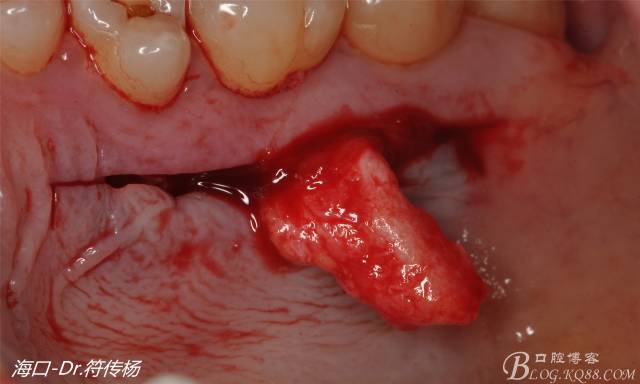

首先用顯微手術(shù)刀切斷手術(shù)范圍內(nèi)的牙周韌帶

然后使用下頜開隧刀剝離牙齦

最后使用牙齦乳頭分離器分離牙齦乳頭

接著從腭部上皮下取出結(jié)締組織

確定取出結(jié)締組織長度是否適當